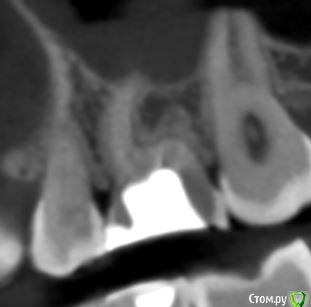

krokomot Опубликовано 19 февраля, 2020 Поделиться Опубликовано 19 февраля, 2020 в медиальном корне недопломбировка и наличие вероятно 4ого канала. Ссылка на комментарий

dmitrib81 Опубликовано 20 февраля, 2020 Автор Поделиться Опубликовано 20 февраля, 2020 Зуб делали много лет назад. Примерно неделю назад появились периодические боли, бывает целый день не болит, потом снова ноющая боль. С приёмом пищи никак не связано. На горячие и холод реакции нетПодскажите, может ещё прислать фоток из КТ Пикассо, а то я в этом ничего не понимаю, просто разных фото экрана прислал, без какого-либо понимания, на что смотреть.. Ссылка на комментарий

dmitrib81 Опубликовано 20 февраля, 2020 Автор Поделиться Опубликовано 20 февраля, 2020 еще фото Ссылка на комментарий